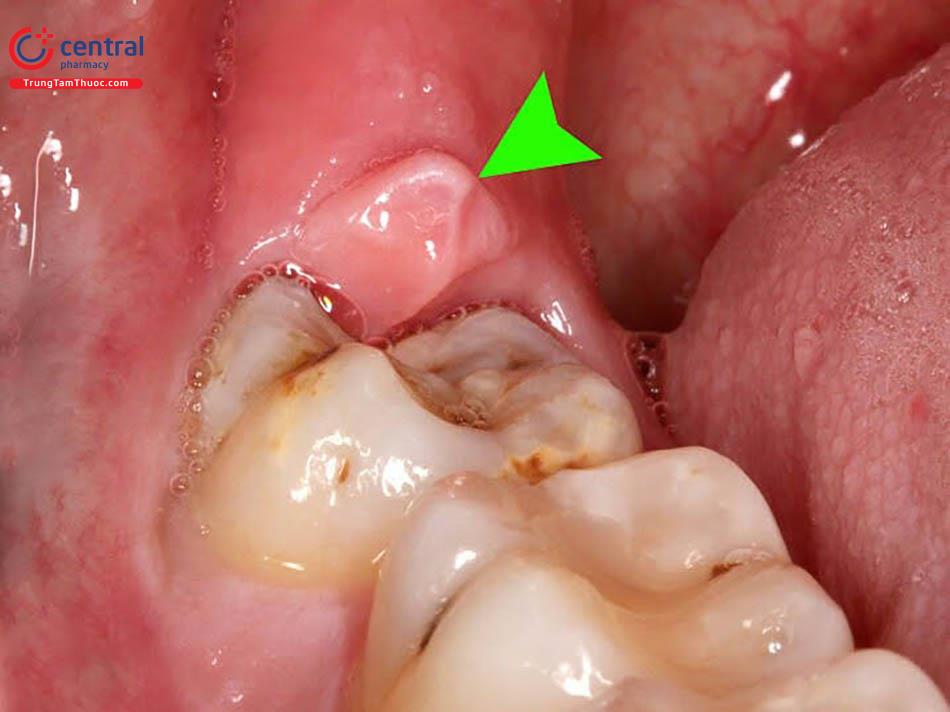

Viêm mạn

Viêm mạn có thể bắt đầu từ các tác nhân gây viêm hoặc là biến chứng của viêm cấp tính.

Ảnh: Viêm họng mạn

Dấu hiệu của bệnh viêm mạn tính là có dịch rỉ nhưng không hoặc ít sưng, nóng và đỏ. Hiện tượng thực bào không mạnh mẽ, không loại bỏ được các tác nhân gây viêm và sự tăng sinh tế bào xơ và mạch máu để phục hồi rất chậm.